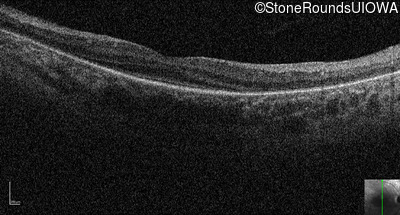

Optical Coherence Tomography - Left - Light Perception

Exemplar